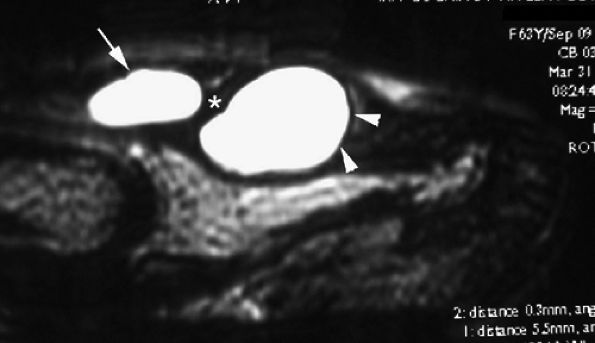

FIGURE 11.47 ● Jersey finger. (A) Sagittal T2-weighted image. (B) Coronal post-contrast T1-weighted images. (C) Axial T1-weighted image. Distal avulsion of the FDP tendon is shown with the proximal end (white arrows) at the metacarpophalangeal joint (type I). The tendon is wavy in the palm (arrowheads). The empty digital canal (in C) may mimic a remnant tendon, but the FDS tendon (asterisk) is alone in the canal.